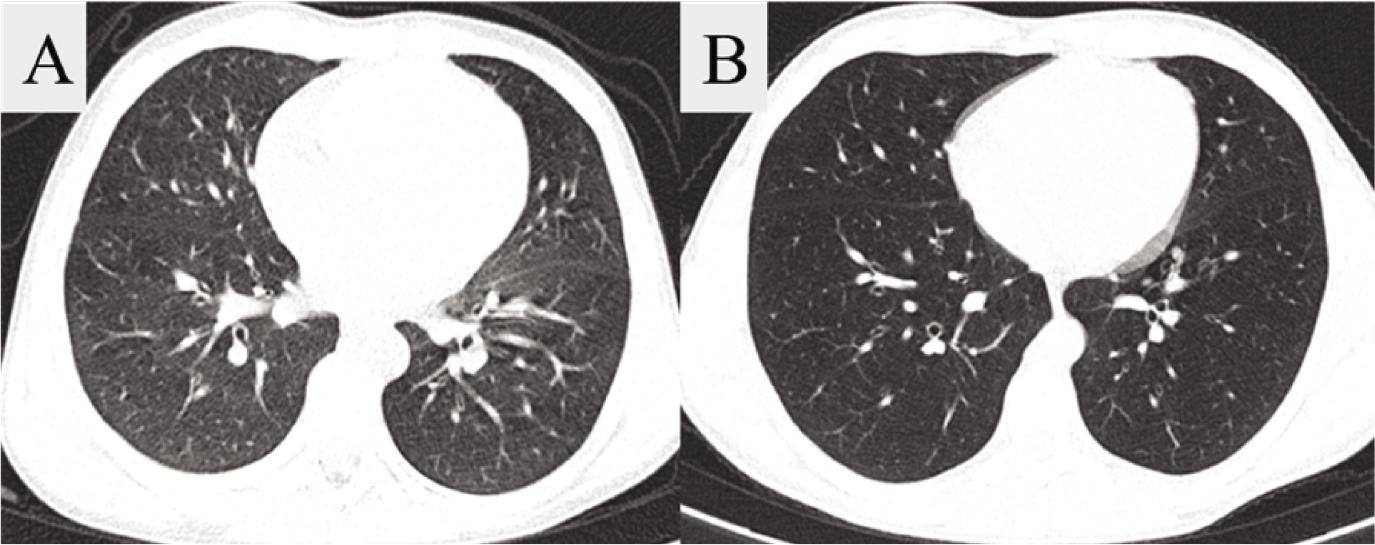

Figure 3.

Figure 4.

| Total Bhalla score | 14.55 | 18.27 | 3.73 | (2.8511, 4.6035) | < 0.001 |

Comparison of mean values of CT parameters assessed before and after therapeutic intervention_

| Bronchiectasis | 1.73 | 1.36 | –0.36 | (–0.6479, –0.0794) | 0.125 |

| Wall thickening | 1.09 | 0.18 | –0.91 | (–1.3039, –0.5143) | 0.008 |

| Mucus plugging | 1.64 | 0.55 | –1.09 | (–1.3948, –0.7877) | 0.002 |